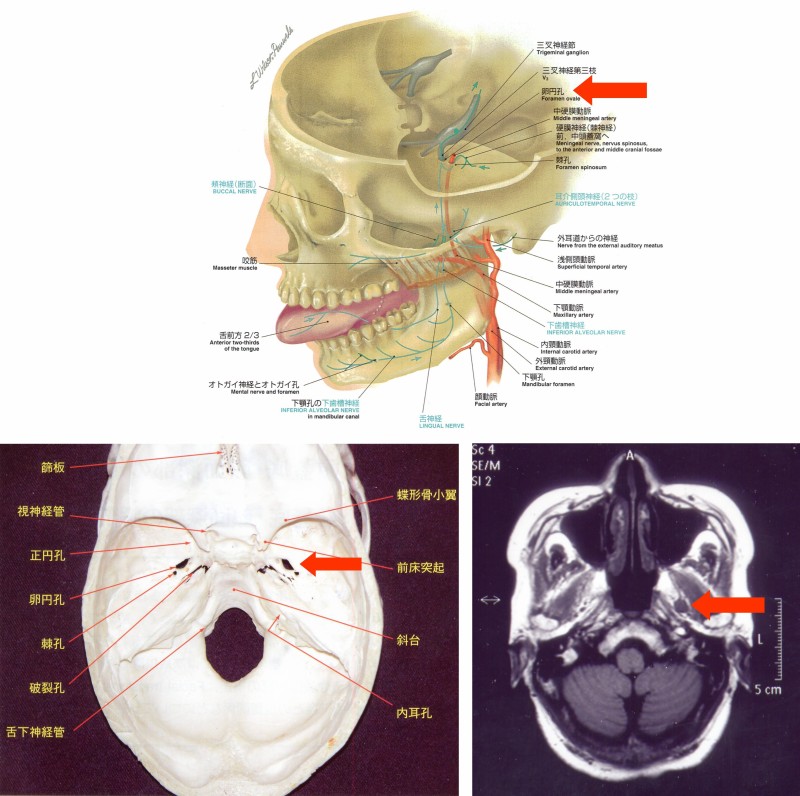

三叉神経鞘腫は、全頭蓋内神経鞘腫(原発性脳腫瘍の10.8%)の0.8%から8%を占める比較的稀な腫瘍とされる(図7)。

図7

当院受診時の所見:聴力正常だったが、左方へ向かう眼振を認めた(図8)。三叉神経の知覚を確認したところ、第2・3枝領域の触覚低下が確認できた(図9)。

図8

図9